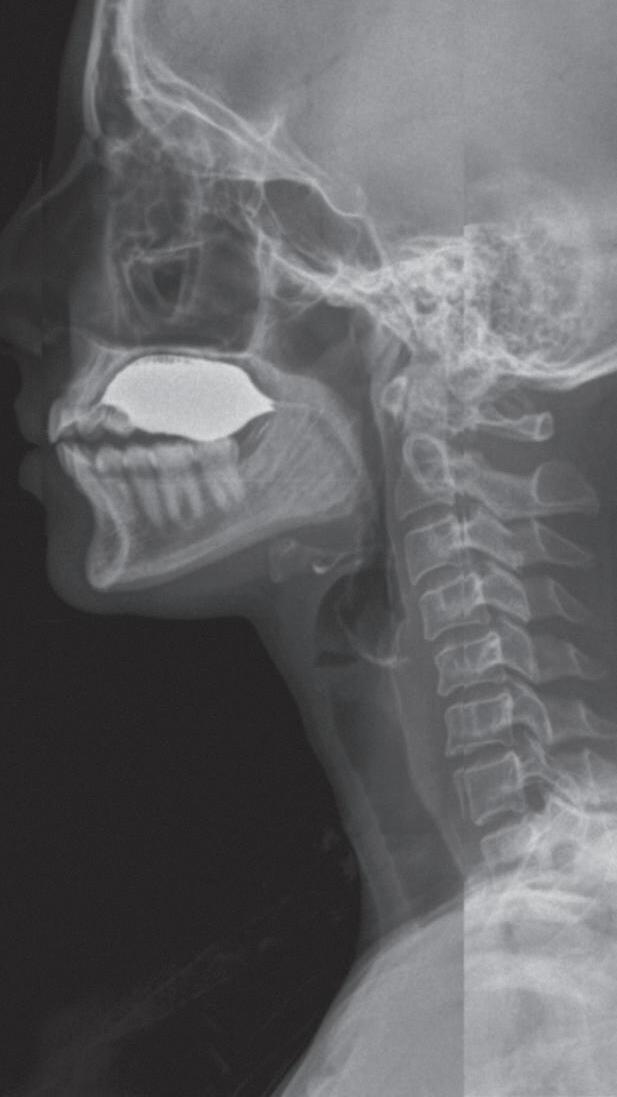

Fig. 1-1. Montagem de duas imagens radiográficas em visão anteroposterior demonstrando o percurso da deglutição desde a cavidade oral até o estômago (a) no adulto e (b) no bebê.

Fig. 1-2. Demonstração das estruturas envolvidas no processo da deglutição nas visões (a) lateral e (b) anteroposterior na imagem radiográfica.